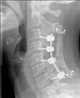

Cervical spine fusion

Anterior cervical discectomy and fusion (ACDF) is a surgical procedure to treat nerve root or spinal cord compression by decompressing the spinal cord and nerve roots of the cervical spine with a discectomy, followed by inter-vertebral fusion to stabilize the corresponding vertebrae. This procedure is used when other non-surgical treatments have failed. [Source: Wikipedia ]